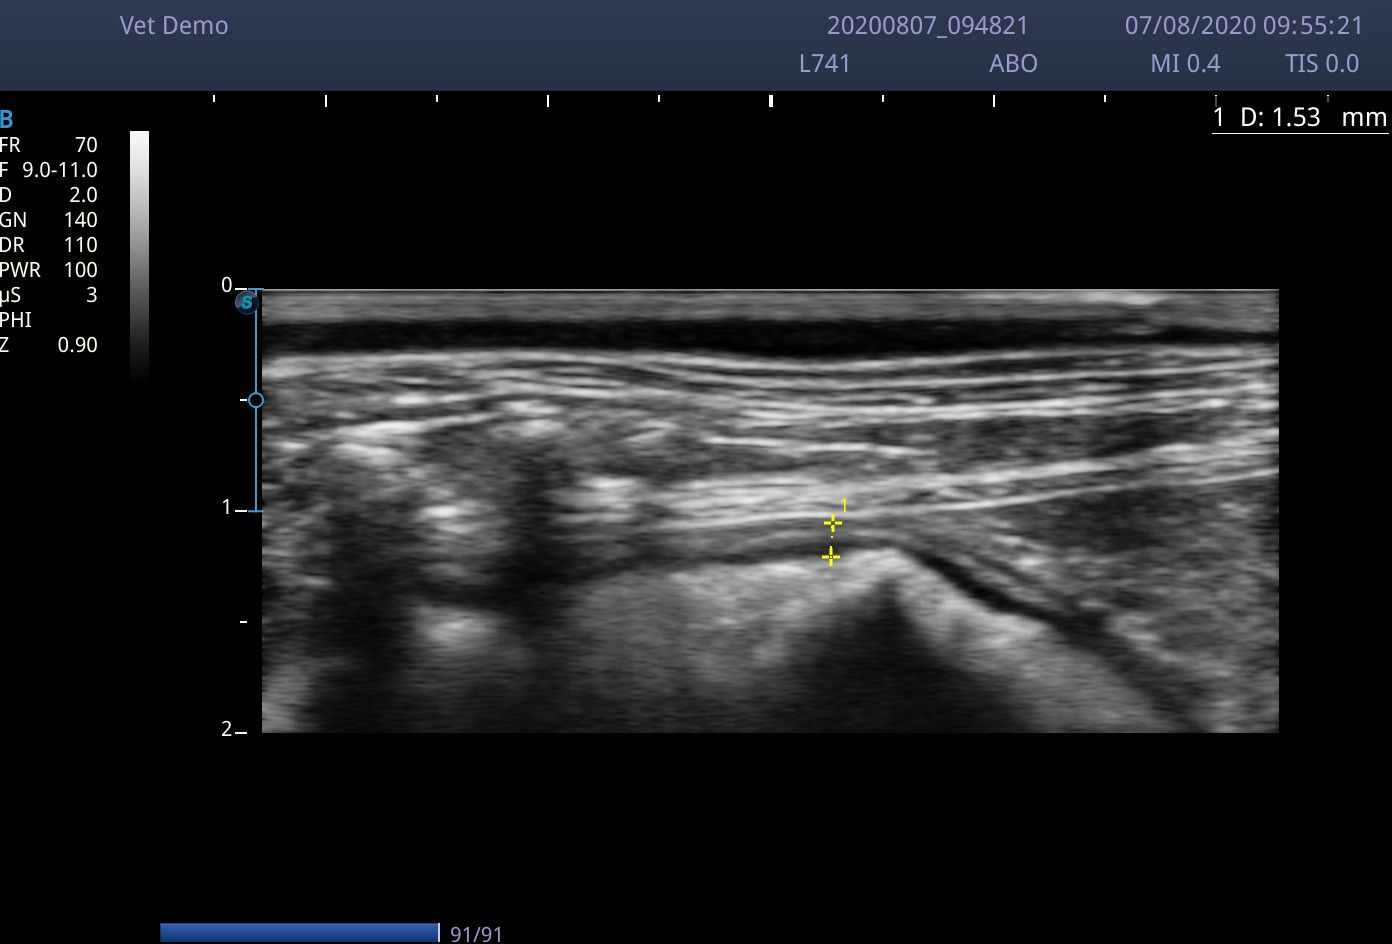

I scanned with the microconvex C613 probe (4-13MHz) and the linear L741 (4-16MHz). Although the linear probe gives great images, the 4.5cm footprint does make maneuverability around a small cat abdomen a little tricky. The microconvex probe was used in a few dogs up to 20Kg and managed to view the liver perfectly well.